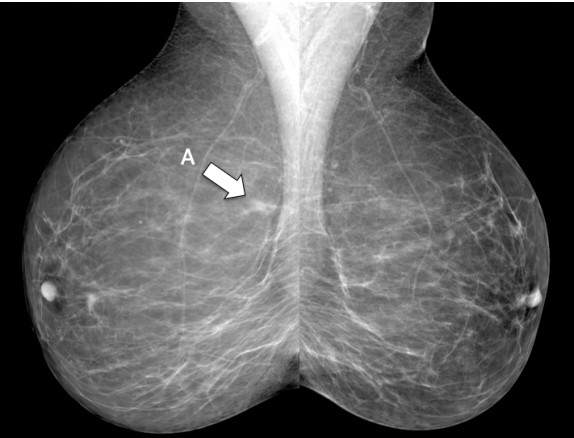

asymmetry

B - architectural distortion

C - microcalcification

D - mass